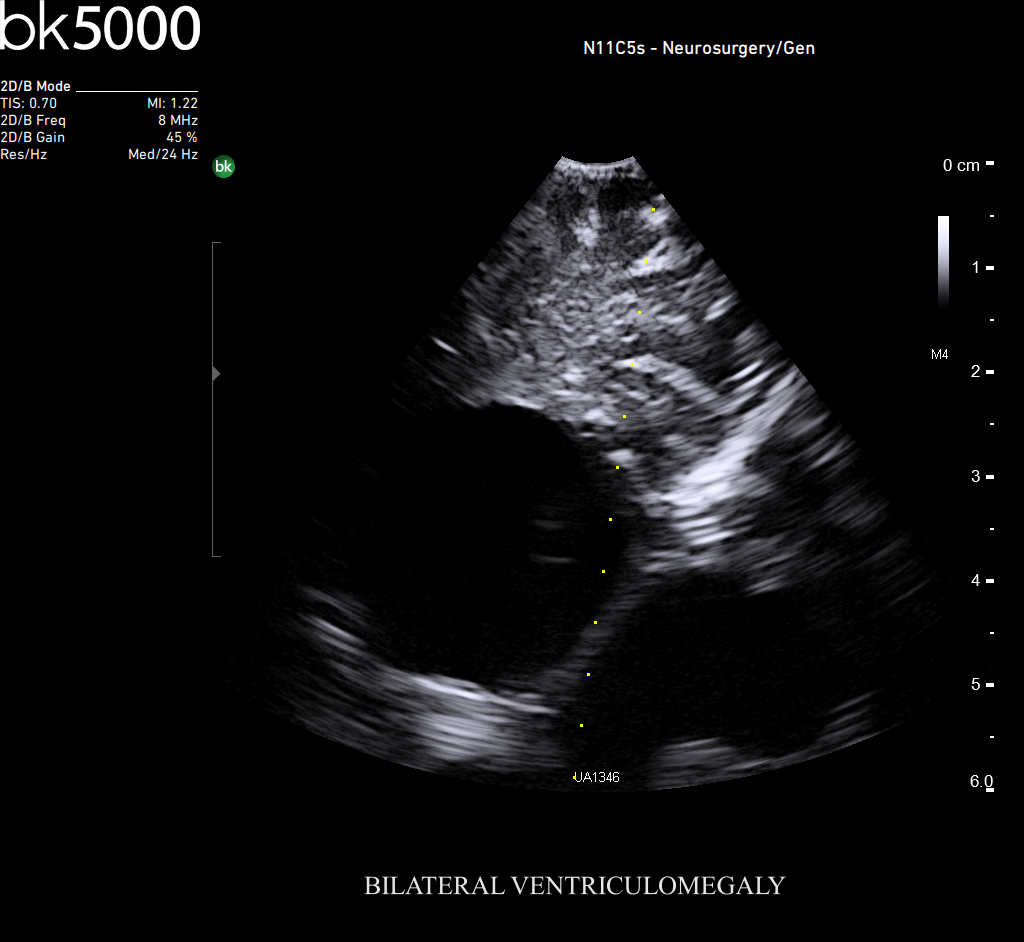

Ultrasound can improve neurosurgical procedures by helping you navigate and identify lesions and anatomical structures in real-time. This is particularly important as the data obtained from a preoperative CT or MRI scan can be outdated at the time of surgery. The bk5000 neurosurgical system provides the highest quality images that allow you to clearly see the margins of a lesion and to determine the best course of action. Using advanced graphics processing technology, this powerful system provides immediate, auto-optimized images that allow you to see the information you need, faster.

Transducers designed for Neurosurgery

The specialized, high-resolution, sterilizable neurosurgery transducers enable you to obtain detailed images of the brain and spinal cord. They have a convenient Smart™ button that lets you activate the transducer, then freeze, store or print the images at the press of a button. Disposable, easy-to-use needle guides assist with targeting lesions.